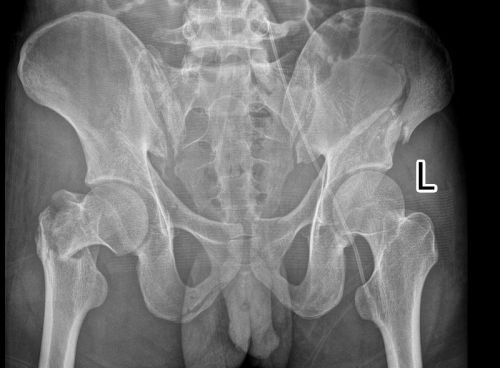

术后1年复查,骨折处愈合良好。